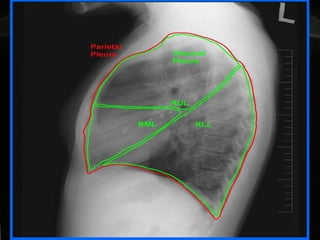

DIAGNÓSTICO POR  IMAGENOLOGÍA Oscar Asensio de la Cruza, Javier Blanco Gonzálezb, Antonio Moreno Galdóc, Javier  Pérez Fríasd, Antonio Salcedo Posadase, Lidia Sanz Borrellf Radiografía   PA y L :  hallazgo típico del derrame pleural:  obliteración del ángulo costofrénico posterior   que da una  imagen de menisco , bien notorio  >  de 175 ml de líquido .

RADIOLOGIA:  Detecta la presencia del derrame y sugiere su etiología  En la radiografía PA y lateral, el hallazgo típico del derrame pleural es la obliteración del ángulo costofrénico posterior (imagen de menisco). Un derrame masivo produce desviación contra lateral del mediastino; la causa más frecuente es la malignidad

RADIOLOGIA:  Se observan hallazgos atípicos: aplanamiento o desplazamiento en la cúpula  aumento de la distancia del diafragma a la burbuja gástrica (2 cm) u opacidad eliptoidea o &quot;pseudotumor&quot;. La proyección en decúbito lateral ayuda en casos de duda.  Importante cuando se va a puncionar (seguridad). .